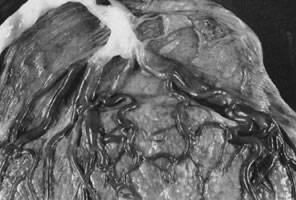

Placenta creta is a clinical diagnosis based on difficulty of delivery of the placenta. If the placenta is delivered and examined pathologically, areas of “incompleteness” of the maternal surface can be noted. The range of findings can extend from missing segments of the placenta to focal irregularities of the basal surface. At the edges of incomplete areas, histologic examination may yield smooth muscle (Fig. 10).61,62 This may be the only confirmation of a diagnosis of placenta creta that can be made when only the placenta is submitted to pathology. If a postpartum curettage or hysterectomy specimen is available, the diagnosis is usually confirmed. Histologically, the lesion may be very focal, with absence of decidualized endometrium, and villi implanted directly onto the myometrial smooth muscle (Fig. 11). The invasive trophoblast can be distinguished from endometrial stromal cells by immunohistochemistry; trophoblasts are cytokeratin positive and endometrial cells are vimentin positive. In a set of 462 births at less than 32 weeks' gestation and 108 singleton uncomplicated births at more than 37 weeks' gestation, excluding stillbirth, multiple gestation, chronic hypertension, diabetes mellitus, and fetal congenital anomalies, 44 of 462 (9.5%) of the preterm placentas had basal myometrial fibers versus 0.9% (1/108) of term controls (p < .001). Uteroplacental vessels with abnormal physiologic change were more frequent in cases with myometrial fibers (p < .003), and placental weights were lighter (p < .03). The incidence of basal myofibers was similar in preterm preeclampsia, premature membrane rupture, preterm labor, and nonhypertensive abruption.61 Experimental models suggest that cytotrophoblasts proliferate in response to hypoxia63,64 and may also directly migrate in response to local oxygen tension.65 One response to local hypoxia may be deeper myometrial invasion. Most of the foci of basal myofibers in our data set were found in the immediate vicinity of a uteroplacental vessel with incomplete or absent physiologic conversion. Basal myofibers may indicate local placental hypoperfusion that has prompted local deeper cytotrophoblast invasion.

Fig 10. Term placenta with adherent smooth muscle ( large star ); note abundant invasive trophoblast ( small star) (hematoxylin and eosin, ×10).